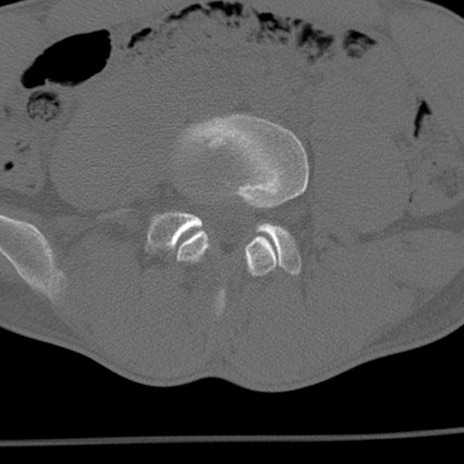

症例3 腰椎CT(横断像)

腰椎CT